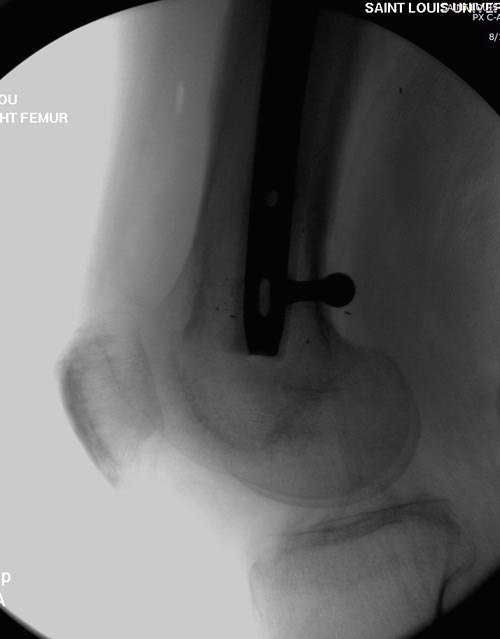

На снимках осложнение огнестрельного перелома бедра поздней инфекцией. 7

лет назад оперирован: правое бедро, сперва на ExFix, затем заменен на

гвоздь, а левая - гвоздь при поступлении.

Беспокойство проявил недавно, по поводу жалоб на боли сделано МРТ и

дренирование абсцесса терапевтами. Мы удалили гвоздь, сделали I&D,